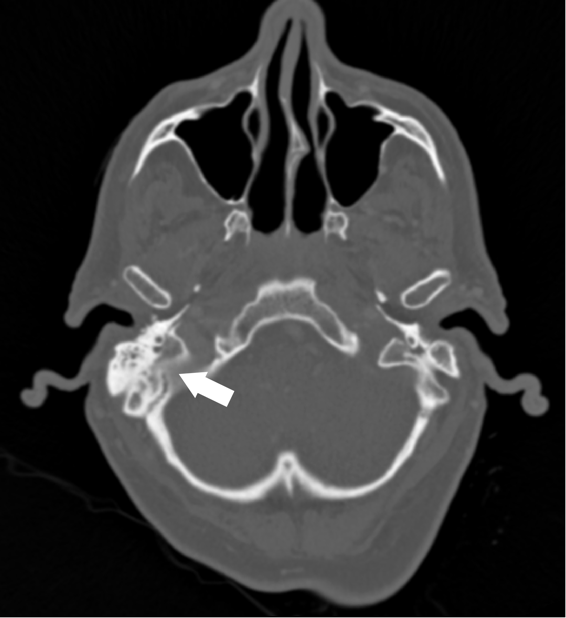

Figure 2. CT of temporal bones with IV contrast demonstrating opacification of the right mastoid air cells and abnormal soft tissue within the epitympanum (arrow).

A 62 year old male with unknown past medical history was dropped off at the emergency department by EMS after being found altered with concern for IV drug use. On presentation he was febrile to 104.5o F, tachycardic, and although he was initially responsive, his mental status deteriorated. Labs were drawn and broad-spectrum antibiotic coverage with vancomycin, cefepime, and metronidazole was initiated in the ED. He then had a tonic-clonic seizure event and was given intravenous levetiracetam. A CT brain showed a right inferior temporal lobe lesion, initially interpreted as likely glioblastoma multiforme, causing subfalcine and uncal herniation. MRI revealed a ring-enhancing mass measuring 3 cm x 3 cm x 3 cm in the right temporal lobe with significant surrounding edema. CT of the temporal bones also revealed right mastoiditis (Figures 1 and 2).